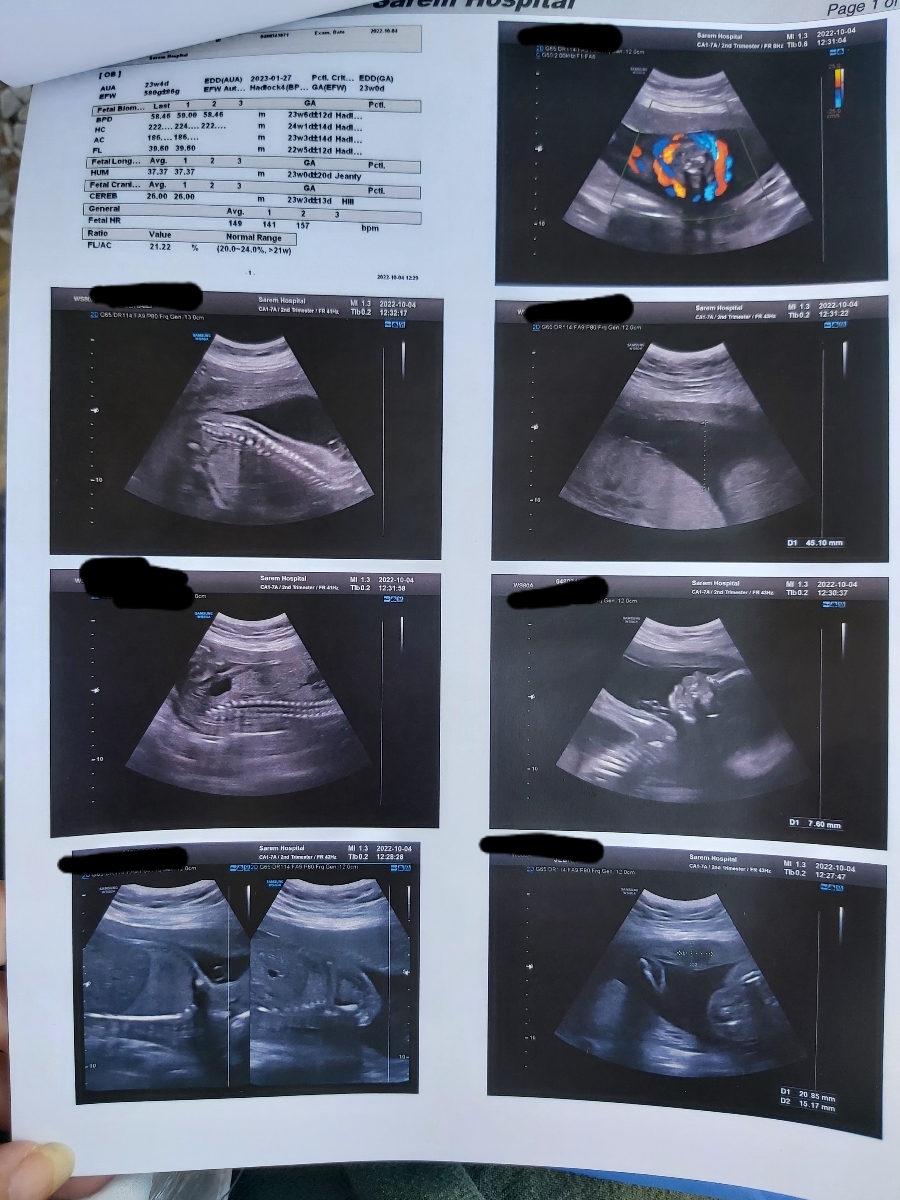

من امروز تکرار دومین آنومالیم بود بخاطر ریسک ntds

این دومی بود.لطفا تفسیرش کنید از دکتر سونوگرافی پرسیدم ولی چون دکتر دسترس نبود امروز ممنون میشم شما از نگرانی دربیاریدم .

تفسیر سونو آنومالی در ۲۴ هفته

در سونوگرافی شما تمام موارد بررسی شده طبیعی هستند

1. یک دور گردش بند ناف دور گرد دیده شده که از آنجا که بند ناف اندامی نرم و بلند است مشکلی ایجاد نمیشود فقط باید از حرکات ناگهانی اجتناب کرده و مراقب حرکات جنین باشید.

2. یک فیبروم در رحم دیده شده که ابعاد آن مشکل ساز نبوده و فقط روند تغییرات آن در سونوگرافی باید تحت نظر باشد.

3. خونرسانی در داپلر خوب است اما بهتر است با نظر متخصص خود انوکساپارین یا آسپرین را شروع کنید. تصميم نهایی با پزشک شما است.

4. خوشبختانه شواهدی به نفع NTDS وجود ندارد.

5. وضعیت رشدی جنین خوب است اما تلاش کنید به تغذیه خود توجه بیشتری داشته باشید 🌸